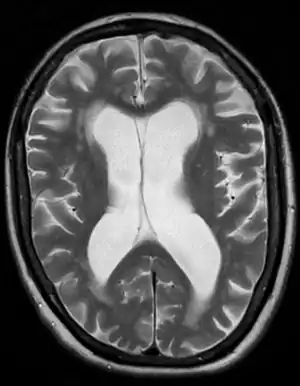

Exceptional case

One case of hydrocephalus was a man whose brain shrank to a thin sheet of tissue, due to a buildup of cerebrospinal fluid in his skull. As a child, the man had a shunt, but it was removed when he was 14. In July 2007, at age 44, he went to a hospital due to mild weakness in his left leg. When doctors learned of the man's medical history, they performed a CT and MRI scan, and were astonished to see "massive enlargement" of the lateral ventricles in the skull. Dr. Lionel Feuillet of Hôpital de la Timone in Marseille said, "The images were most unusual... the brain was virtually absent."[39] Intelligence tests showed the person had an IQ of 75, considered "borderline intellectual functioning", just above what would be officially considered mentally challenged.

The person was a married father of two children, and worked as a civil servant, leading an at least superficially normal life, despite having enlarged ventricles with a decreased volume of brain tissue. "What I find amazing to this day is how the brain can deal with something which you think should not be compatible with life", commented Dr. Max Muenke, a pediatric brain-defect specialist at the National Human Genome Research Institute. "If something happens very slowly over quite some time, maybe over decades, the different parts of the brain take up functions that would normally be done by the part that is pushed to the side."[40][41][42]